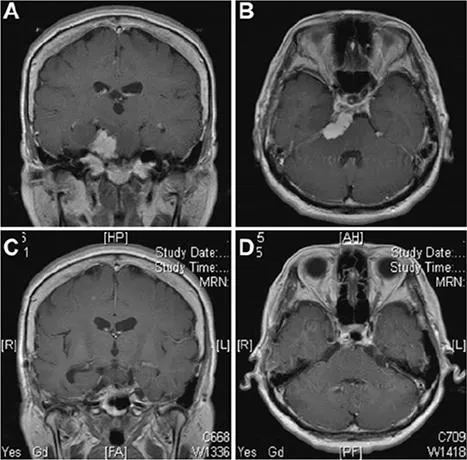

一名53岁女性患者,临床表现为搏动性头痛,并观察到左眼视力出现急剧下降。磁共振成像显示一个均匀强化的肿块,病灶集中于岩斜上交界处,广泛植入并附着于上斜坡及天幕上(参见图5A和B)。手术采用了Kawase入路。在滑车神经入幕点附近切开小脑幕后,可见三叉神经向双侧下方移位,部分被肿瘤包裹,肿瘤与上斜坡相连,并存在部分钙化。肿瘤切除后,观察到外展神经向下移位。术后磁共振成像(图5C和D)显示肿瘤已完全切除,未发现任何脑组织损伤。

患者术后出现部分侧视麻痹,该症状在1个月后完全消失,视力恢复正常。该肿瘤起源于硬膜内间隙,位于图3所示的B2和C1区域。在此病例中,Kawase入路是一种适宜的手术方法。

图5:案例1。 采用Kawase入路手术切除肿瘤。术前磁共振增强冠状位(A)及轴位(B)图像提示岩斜区存在一均匀强化的肿瘤,起源于岩尖,附着于小脑幕上。肿瘤推挤脑干,并侵犯海绵窦。术后磁共振(C和D)图像显示肿瘤已实现全切。